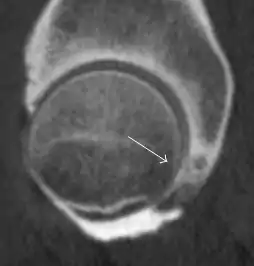

Synovial chondromatosis can be confidently diagnosed by X-ray when calcified cartilaginous chondromas are seen. However, other synovial proliferative processes, such as pigmented villonodular synovitis, require MRI for accurate diagnosis, although noncalcified synovitis can be suspected in radiographs by indirect signs, such as soft tissue swelling and/or erosions in the femoral head, femoral neck, or acetabulum (Figure 7).[1]

Figure 7:

Axial CT image of pigmented villonodular synovitis eroding the posterior cortex of the femoral neck.[1]

Sagittal T2* gradient echo image showing a posterior soft tissue mass with hypointense areas secondary to hemosiderin deposition.[1]

In synovial proliferative disorders, MRI demonstrates synovial hypertrophy. In the case of PVNS, characteristic foci of low signal intensity related to hemosiderin deposition are better seen on gradient echo T2* images (Figure 7). In the case of synovial osteochondromatosis, the synovial hypertrophy is accompanied by intermediate signal cartilaginous loose bodies and/or low signal calcified loose bodies.[1]